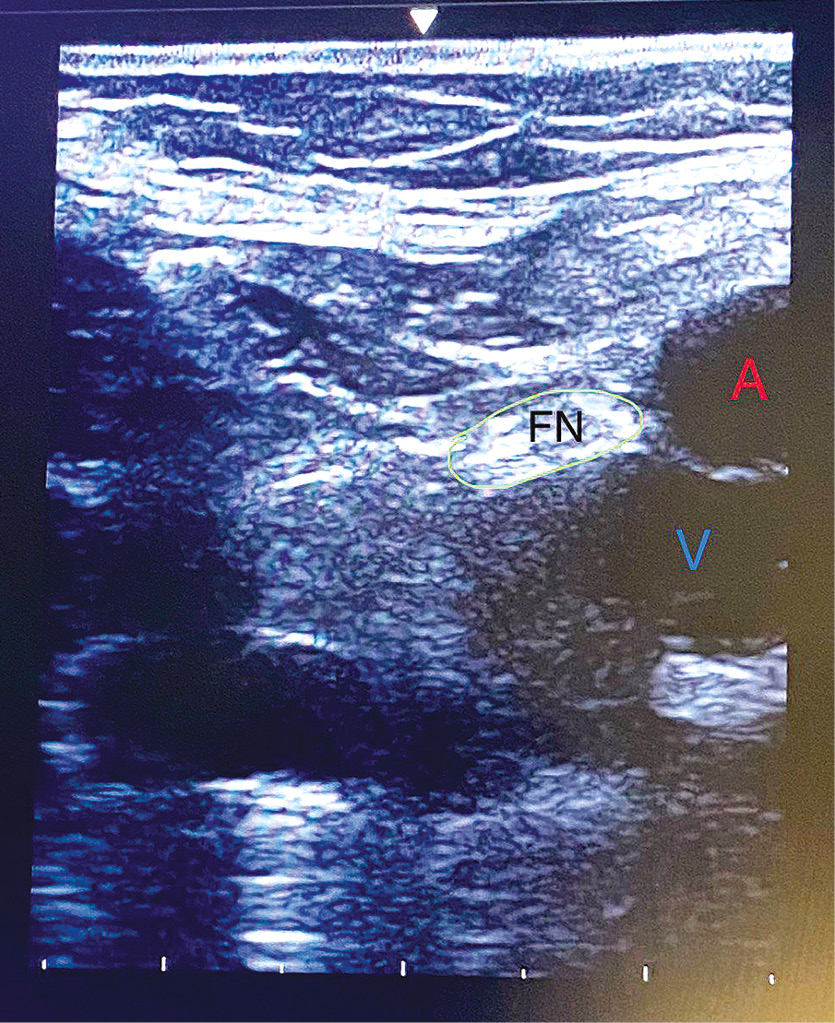

ПББН выполняли перед операцией под контролем УЗ-навигации: в положении пациента лёжа на спине при помощи высокочастотного линейного датчика визуализировали структуры пахового треугольника. Поиск бедренного нерва осуществляли по методике in-plane иглой с использованием нейростимулятора (Stimuplex-DIG, B. Braun Medical, Германия). В непосредственной близости от бедренного нерва под подвздошной фасцией вводили 20 мл раствора ропивакаина (5 мг/мл) и через интродьюсер в периневральном пространстве на 2–4 см вводили и фиксировали катетер (рис. 1).

Рис. 1. Ультразвуковая картина бедренного нерва. A — бедренная артерия, V — бедренная вена, FN — бедренный нерв.